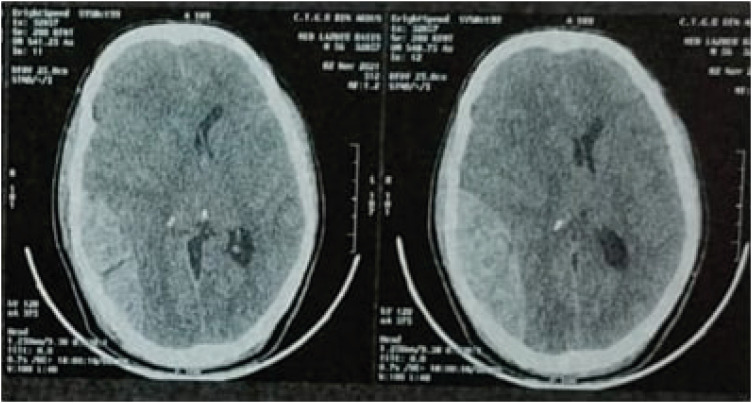

Abstract Image